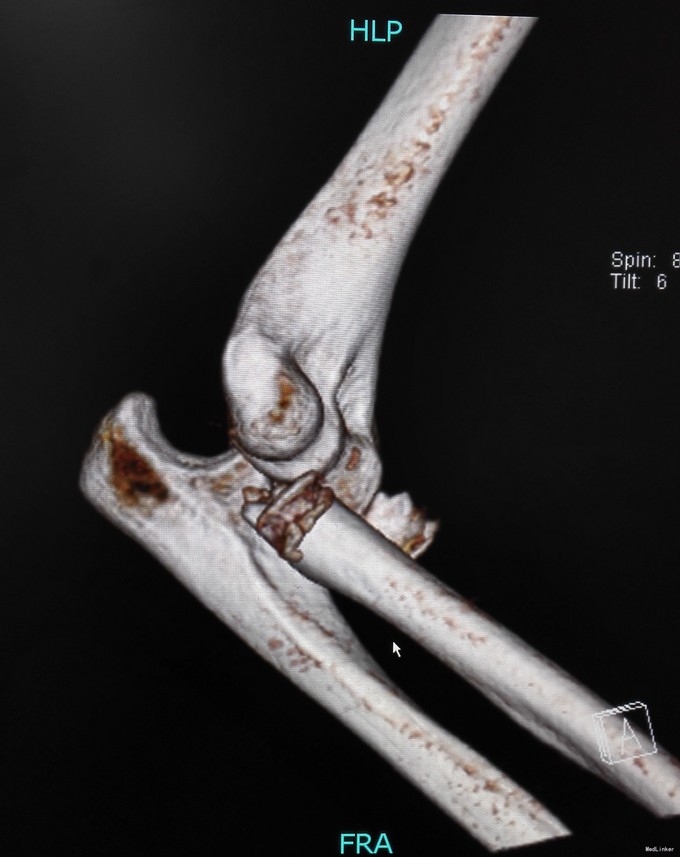

肘关节恐怖三联征行桡骨小头假体置换

女性,67岁,车祸致右肘肿痛畸形1天入院

诊断为肘关节恐怖三联征(肘关节后脱位伴桡骨头和尺骨冠状突骨折),消肿后予以切开复位Wright桡骨小头假体置换,外侧副韧带修补,冠状突骨块小,未行固定。

术后近两年,桡骨近端假体承载处骨赘增生,但患者功能良好,无不适主诉,疗效满意